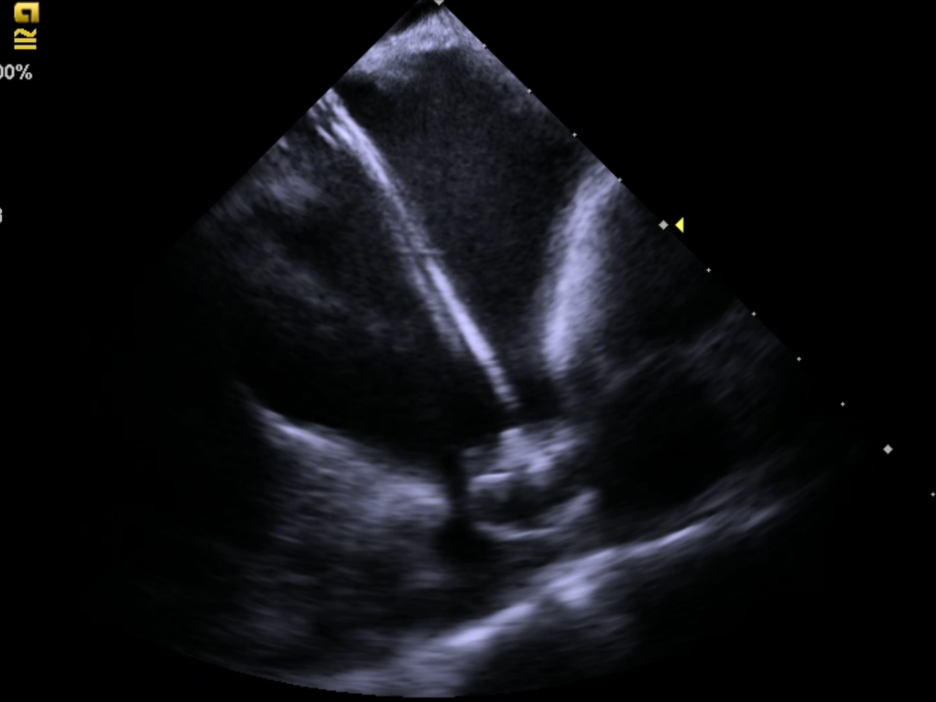

近年来心腔内三维超声技术(ICE)是国际心内介入领域兴起的一项新技术。它在心内导管介入的基础上,把腔内超声探头送到心脏的特定部位,结合心腔内三维标测技术对于用于复杂的心律失常的治疗和房颤治疗。让医生得以在手术中清晰观察心脏内的特殊结构,实时监测心脏情况。被誉为潜入心脏的眼睛,术者可以慧眼识心,患者安全倍增。

2021年6月17日中午12:30,88岁高龄的患者在局麻下,经心腔内超声(ICE)引导行左心耳封堵。术程顺利。当手术结束后,心内科导管室内所有医护人员都不约而同地为彭建军主任精彩而成功的手术鼓起掌来。